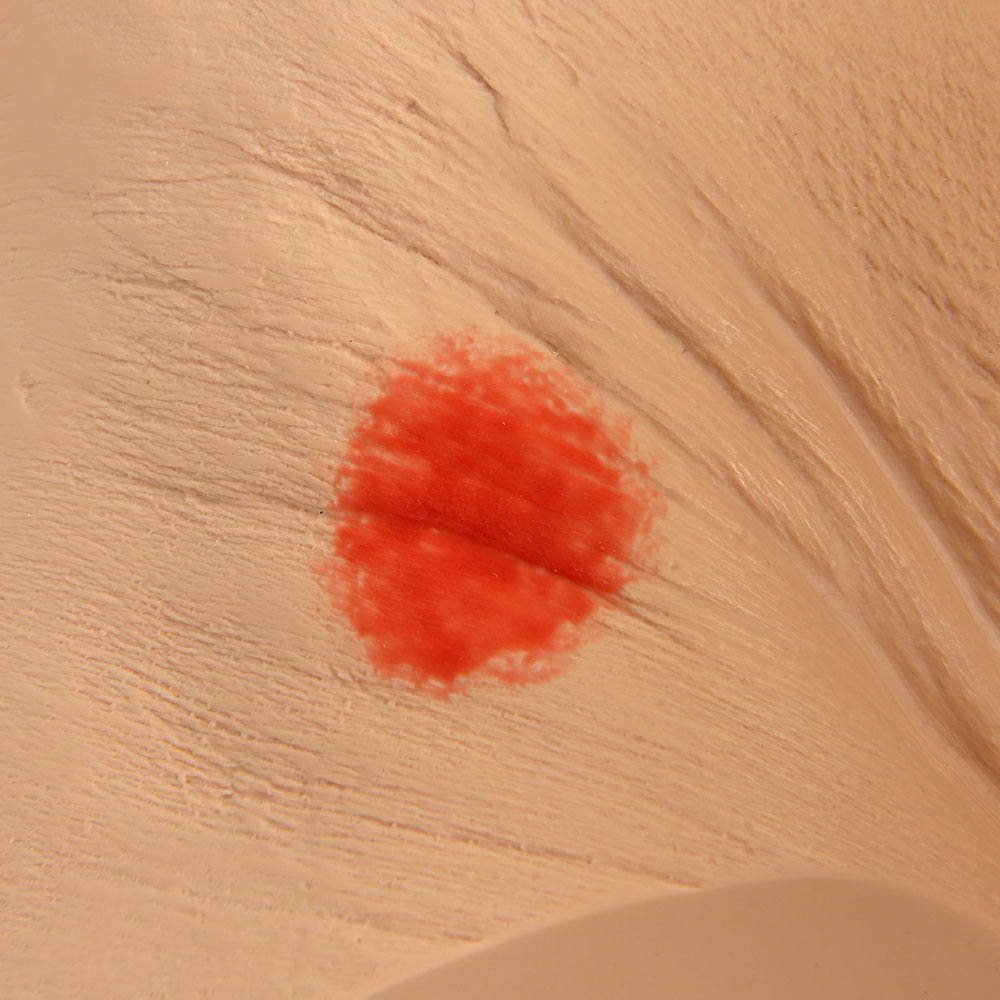

The Seymour II™ Wound Care Model is a highly realistic pressure injury simulator moulded from a 74-year-old patient. It accurately replicates the look and feel of human tissue and presents a wide range of pressure injuries, including Stages 1–4, DTPI, unstageable wounds, and a dehisced wound for advanced wound care training.

- Great care has been taken to hand paint each wound just as you would see it on a patient for the most life-like patient training scenario

- The Seymour patient simulation model makes it possible to visualize and understand the differences in wounds

- Wound care simulation model displays the following pressure injuries:

- Stage 1

- Stage 2